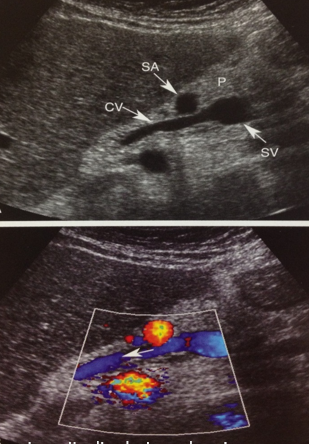

cavernous transformation of PV

portal vein thrombosis (PVT)

portal vein stenosis (PVS)